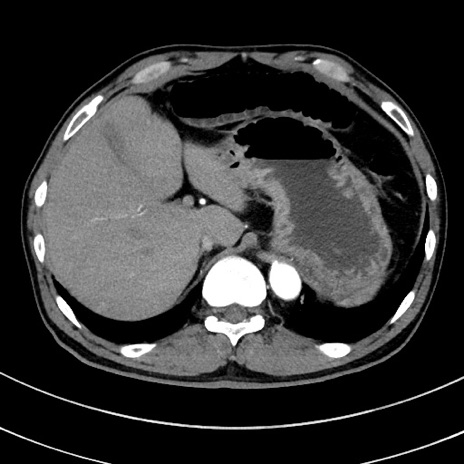

症例8(横断像)

【症例】 60歳代男性

【主訴】 黒色吐物

【現病歴】 4日前から嘔気自覚、2日前の朝食後にも嘔気あり、自分で手で嘔吐反射起こし嘔吐したところ血が混ざっていたため受診。

【既往歴】 5年前汎発性腹膜炎を伴う急性虫垂炎で手術、高血圧、前立腺肥大症、高脂血症

【身体所見】 腹部正中に手術癩痕あり 腹部平坦・軟圧痛なし膨満感あり

【データ】WBC 8400、CRP 4.54